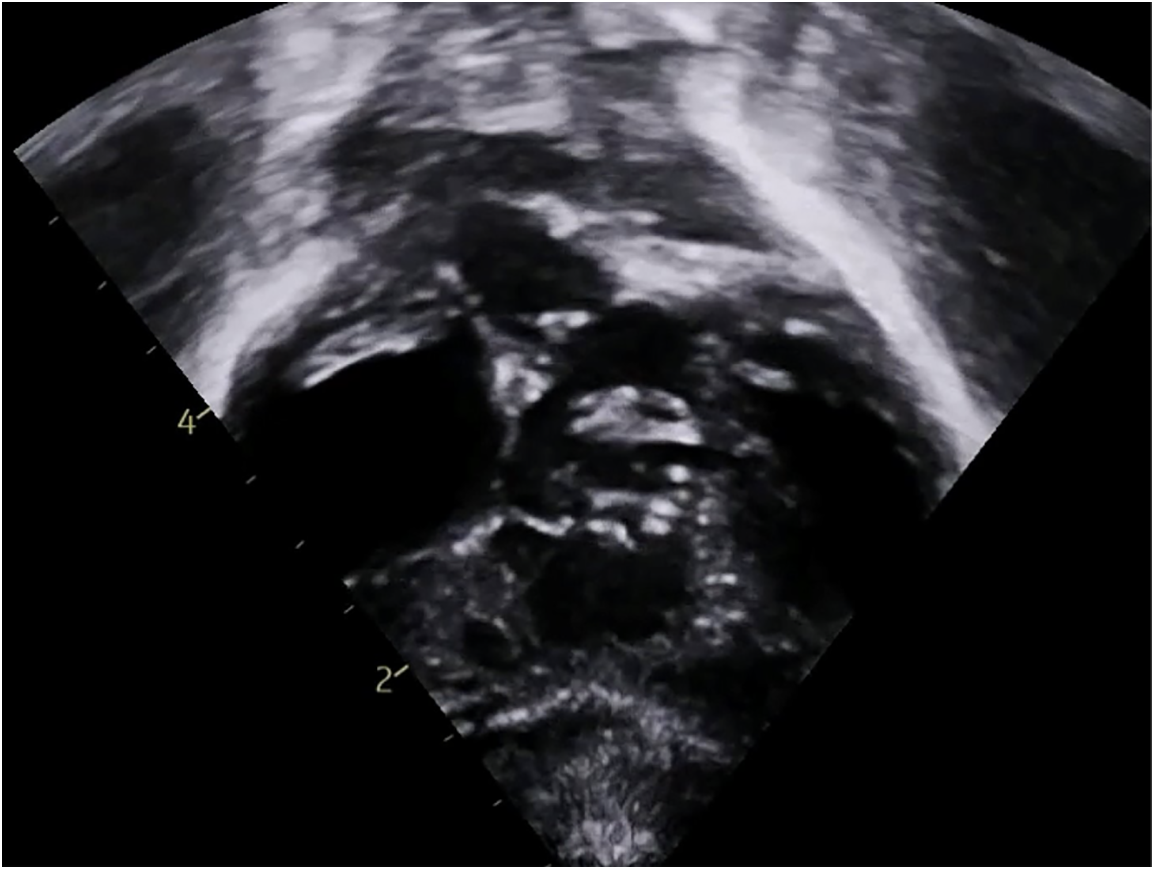

Figure 3: Transthoracic echocardiogram showing Tetralogy of Fallot with atrioventricular septal defect